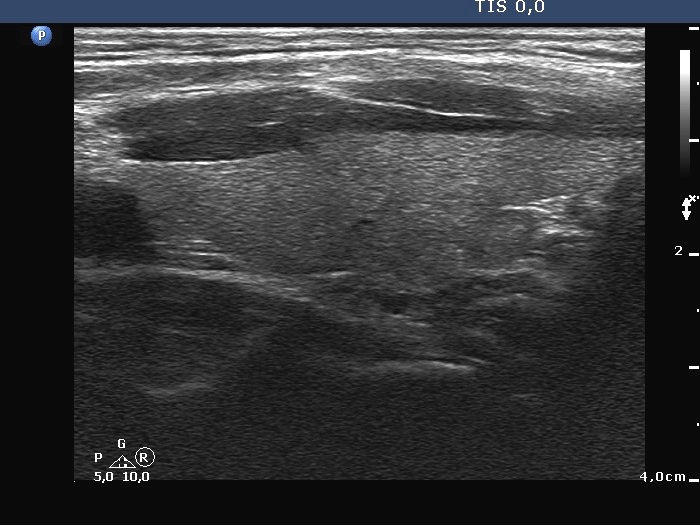

The composition of the nodule - case conp 050 (ultrasonographic picture 9)

Left lobe, longitudinal scan.